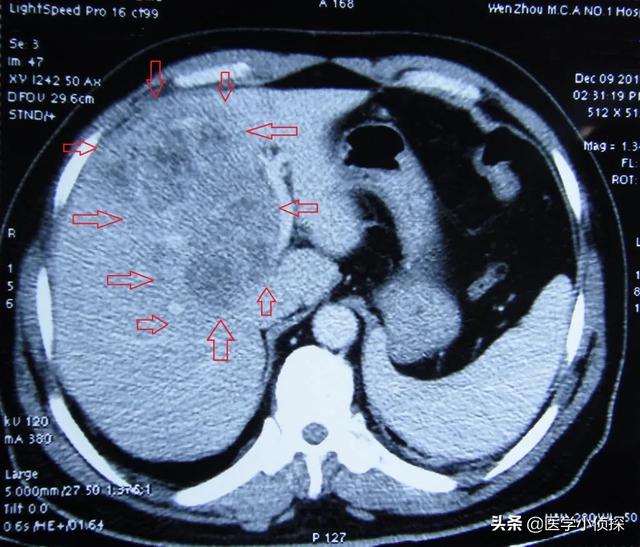

(Comme indiqué : cancer du foie métastatique)

- Si une échographie du foie ne révèle pas de tumeur dans le foie, ou si la nature de la tumeur ne peut être déterminée, une alpha-fœtoprotéine élevée est hautement suspecte de la présence possible d'un carcinome hépatocellulaire.Une tomodensitométrie du foie peut être réalisée.Je recommanderais d'emblée une tomodensitométrie améliorée du foie, car cette technique est relativement efficace pour identifier les tumeurs hépatiques.